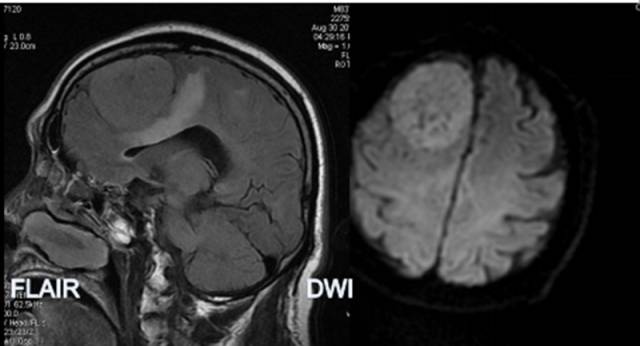

病例3:

TIWI C 显示病灶呈实质性增强,FLAIR呈高信号,边缘见血管伸入。MRS 病灶内波谱显示Cho峰明显升高,无NAA峰, 出现GHS、Gly峰,并见到Lip峰。结合常规MRI所见,以及 Lip峰不高和瘤周(体素4)浸润不明显,提示含脂肪化生细胞较多的良性脑膜瘤可能为大,但恶性脑膜瘤不能除外。病理图片显示泡沫细胞,可能为出现Lip峰的原因。